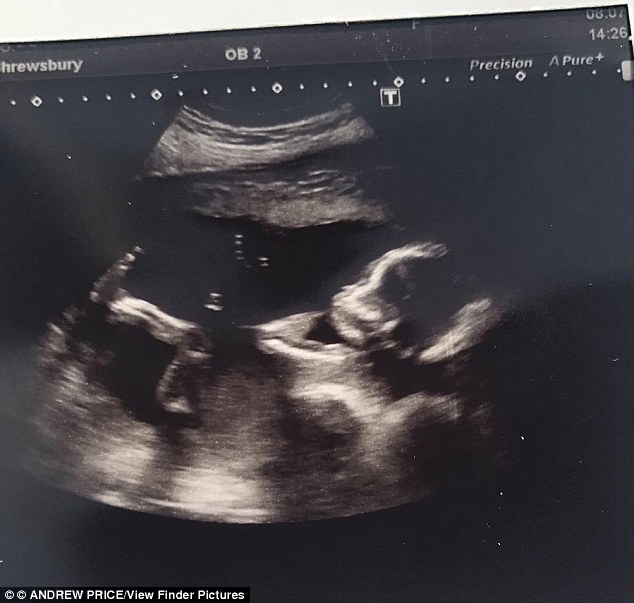

Devan Cadwallader, në 25-vjeçaree angleze nga Telford, kishte shkuar në spital, e shqetësuar pasi nuk ndjente më të lëvizte vogëlushen që mbante në bark. Por mjekët e dërguan në shtëpi, duke i thënë se nuk kishte gjë, kur në fakt vogëlushja kishte vdekur.

“Nuk e dimë më se kush e ka fajin, por dimë vetëm që hymë në spital me vogëlushen shëndoshë e mirë dhe dolëm prej andej me një arkivol”, tha gruaja për mediat vendase, e cila ndodhej në muajin e fundit të shtatzënisë.

E shqetësuar për shkak se vogëlushja nuk po lëvizte, Devan shkoi në spital me të shoqin, por personeli e injoroi pa e vizituar, duke i thënë se nuk kishte asgjë, ndaj duhej të kthehej në shtëpi.

Pas dy ditësh, duke mos ndjerë më lëvizet e së voglës, shkoi sërish për kontroll, ku rrahjet e zemrës së bebes nuk dëgjoheshin.

Vogëlushja kishte vdekur brenda në bark, pa ardhur ende në jetë! E shkatërruar familja denoncoi spitalin, me synim që të kërkojë të drejtësi, shkruan noa.al.